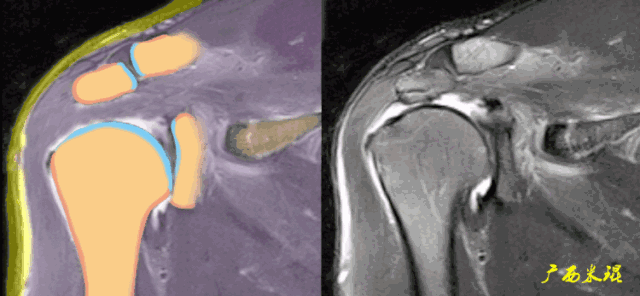

肩关节MRI检查扫描平面

(2)斜矢状位:垂直于冈上肌长轴,观察肩峰形态及喙肩弓,观察肩袖4个组分的短轴断面。

正常肩袖的MRI表现

各个序列肩袖均表现为均匀的低信号,是肌腱的延续。